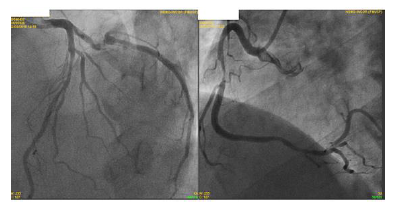

Paciente do sexo feminino, 65 anos, com antecedente de hipertensão arterial, tabagismo, diabética e com histórico familiar de doença arterial coronariana. Vem em consulta ambulatorial com histórico de angina de início há 6 meses, atualmente aos moderados esforços, CCS II (Canadian Cardiovascular Society), sem dispneia ou demais queixas. Em uso ambulatorial de aspirina 100mg ao dia, atorvastatina 40mg ao dia, metformina 850mg 3x ao dia, enalapril 20mg 2x ao dia e anlodipino 10mg ao dia. Exames laboratoriais revelam: LDL colesterol de 88 mg/dl, HDL colesterol de 51 mg/dl, triglicérides de 177 mg/dl, glicemia de jejum de 140 mg/dl e hemoglobina glicada de 7,4%. Ao exame físico, Pressão arterial de 150/70 mmHg, frequência cardíaca de 79 batimentos por minuto. Demais sem alterações.

Durante a investigação, a paciente apresentou piora da angina, atualmente em CCS III e manteve-se refratária às medicações. Realizou o cateterismo (imagem abaixo).

I. Paciente apresenta lesão grave em artéria coronária direita e a revascularização percutânea dessa lesão pode ser realizada visando melhora de sintomas.

II. Paciente apresenta lesão em artéria coronária descendente anterior. O uso de métodos fisiológicos, como reserva de fluxo coronário (FFR) pode ser indicado para melhor avaliação e caso FFR menor que 0,8 a revascularização está indicado.

III. Em situações de lesões triarteriais, com acometimento de coronária descendente anterior (DA) em porção proximal, há indicação de revascularização. Deve-se calcular o Synthax escore e caso ele for maior que 32, há indicação de revascularização percutânea (via hemodinâmica) e caso menor que 32, há indicação de revascularização cirúrgica.

IV. Independente do tipo de revascularização a ser indicada (percutânea ou cirúrgica), o paciente deve receber dupla antiagregação plaquetária por 1 ano, com indicação Classe IA de diretrizes.